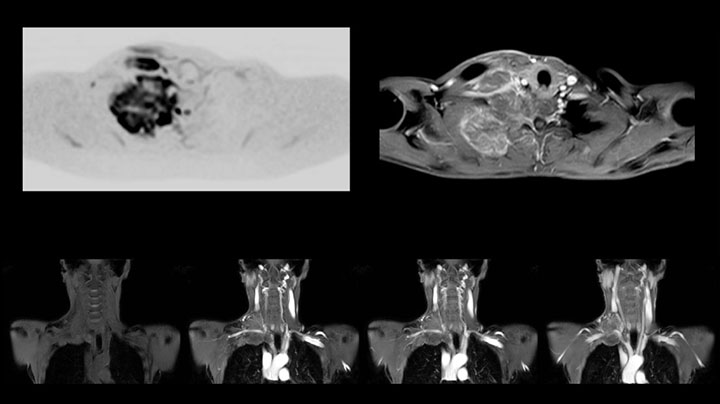

MRI of Pancoast tumor

Although the area between the neck and the top of the lung is one of the most difficult areas for MRI, Prodiva 1.5T images show good quality in this 56-year-old male with Pancoast tumor on the right. mDIXON TFE images shows excellent fat suppression in the neck area and the DWI shows almost no distortion.

Prodiva MRI pancoast tumor DWI, Seirei Mikatahara

Prodiva MRI pancoast tumor mDixon, Seirei Mikatahara

Prodiva MRI pancoast tumor dynamic, Seirei Mikatahara